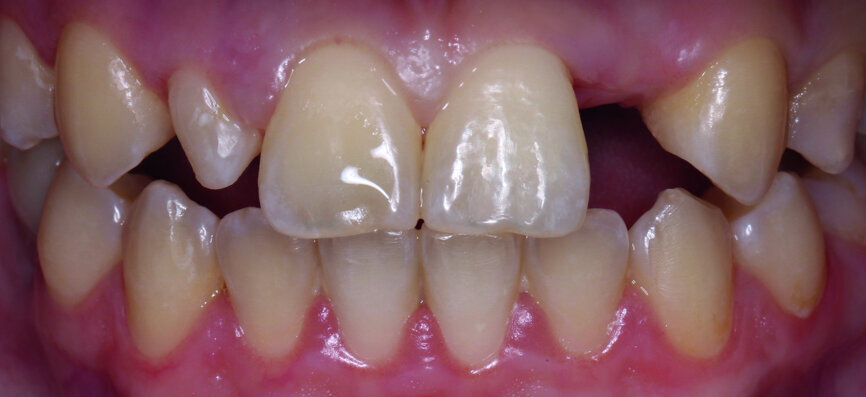

The clinical case features a female patient, who complained about missing tooth #22, as well as the shield-like shape of tooth #12 (Figs. 1 & 2). During the initial examination, the area around the missing tooth was estimated to be quite narrow for an implant. However, the patient declined orthodontic preparation, as she had already previously had orthodontic treatment with orthodontic surgery.

Fig. 1: The patient’s upper teeth before treatment.

Fig. 2: The patient’s upper teeth before treatment.